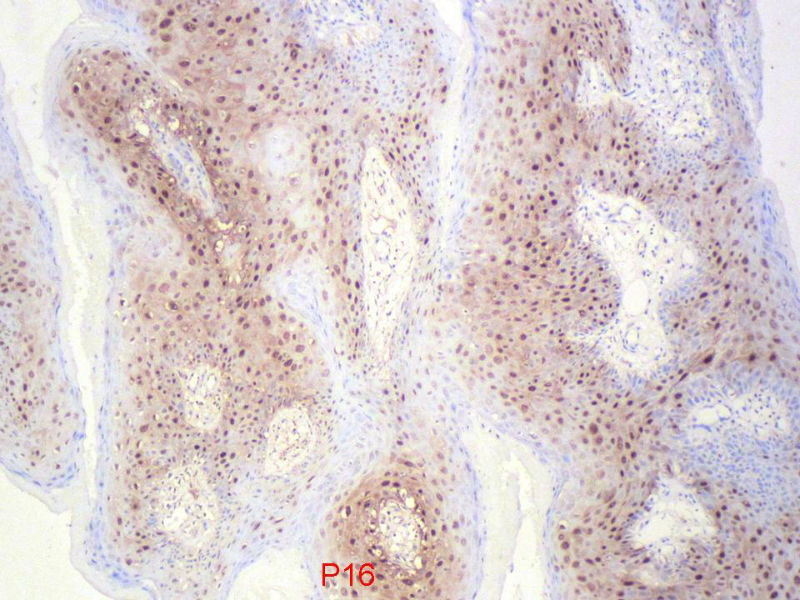

您看了这样的免疫组化结果,会有什么样的考虑呢?

乳头状瘤,有轻度异形,有恶变倾向

乳头状瘤,轻度异形,有恶变倾向

乳头状瘤,上皮内可见挖空样细胞,建议HPV检测